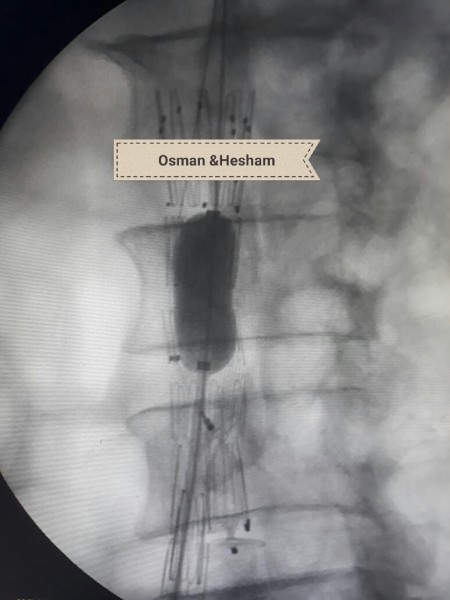

وحول خطوات الجراحة أضاف الدكتور عثمان انه فور إجراء أشعه الدوبلكس للمريض على للشريان الحرقفى الأيسر والشريان الأورطى تبين وجود تمدد ووجود قرحه نشطة بالشريان مع تصلبات شديدة غير مستقرة وانسداد بالدعامة السابقة وكذلك تم إجراء أشعه مقطعية على الشريان الأورطى والطرفين بالصبغة والتي أكدت نفس النتائج ، فكان القرار استخدام دعامات مغطاة للشريان الأورطى والشريان الحرقفى الأيمن وذلك نظراً لأن الوضع الصحي للمريض لا يسمح بإجراء تدخلات جراحية للشريان الأورطى ، ثم تم عمل زرع شريان من الطرف الأيمن للطرف الأيسر لصعوبة شق الدعامة السابقة لاختلاف كبير فى المقاسات التي تم تركيبها للمريض فى وقت سابق .